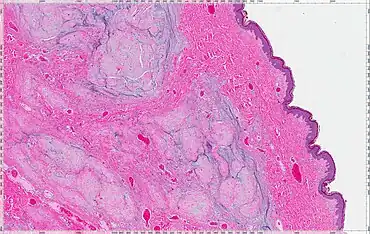

A cutaneous myxoma, or superficial angiomyxoma, consists of a multilobulated myxoid mass containing stellate or spindled fibroblasts with pools of mucin forming cleft-like spaces. There is often a proliferation of blood vessels and an inflammatory infiltrate. Staining is positive for vimentin, negative for cytokeratin and desmin, and variable for CD34, Factor VIIIa, SMA, MSA and S-100.[1]